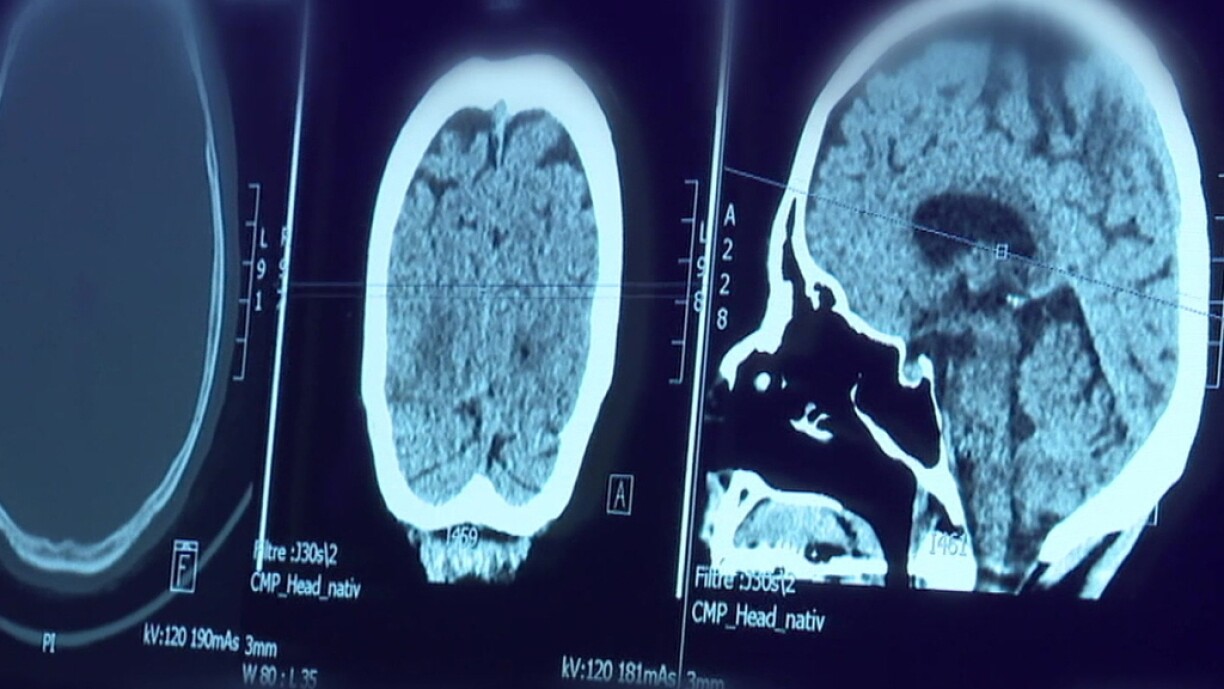

The four founding doctors of the Potaschberg Medical Centre have created a comprehensive concept in Grevenmacher, comprising various specialists, a blood test laboratory, and a medical imaging service. However, the medical imaging department, featuring MRI and scanner equipment, has been attached to the CHL since January through a governing convention.

Dr Frédéric Hencks, a radiologist and co-investor, hails the partnership as a win-win situation, asserting, “we have gained a formidable ally in the CHL. Their IT infrastructure and extensive resources are valuable assets that we didn’t have previously.” Conversely, the CHL has also benefited from this collaboration by gaining access to ready-made imaging facilities.